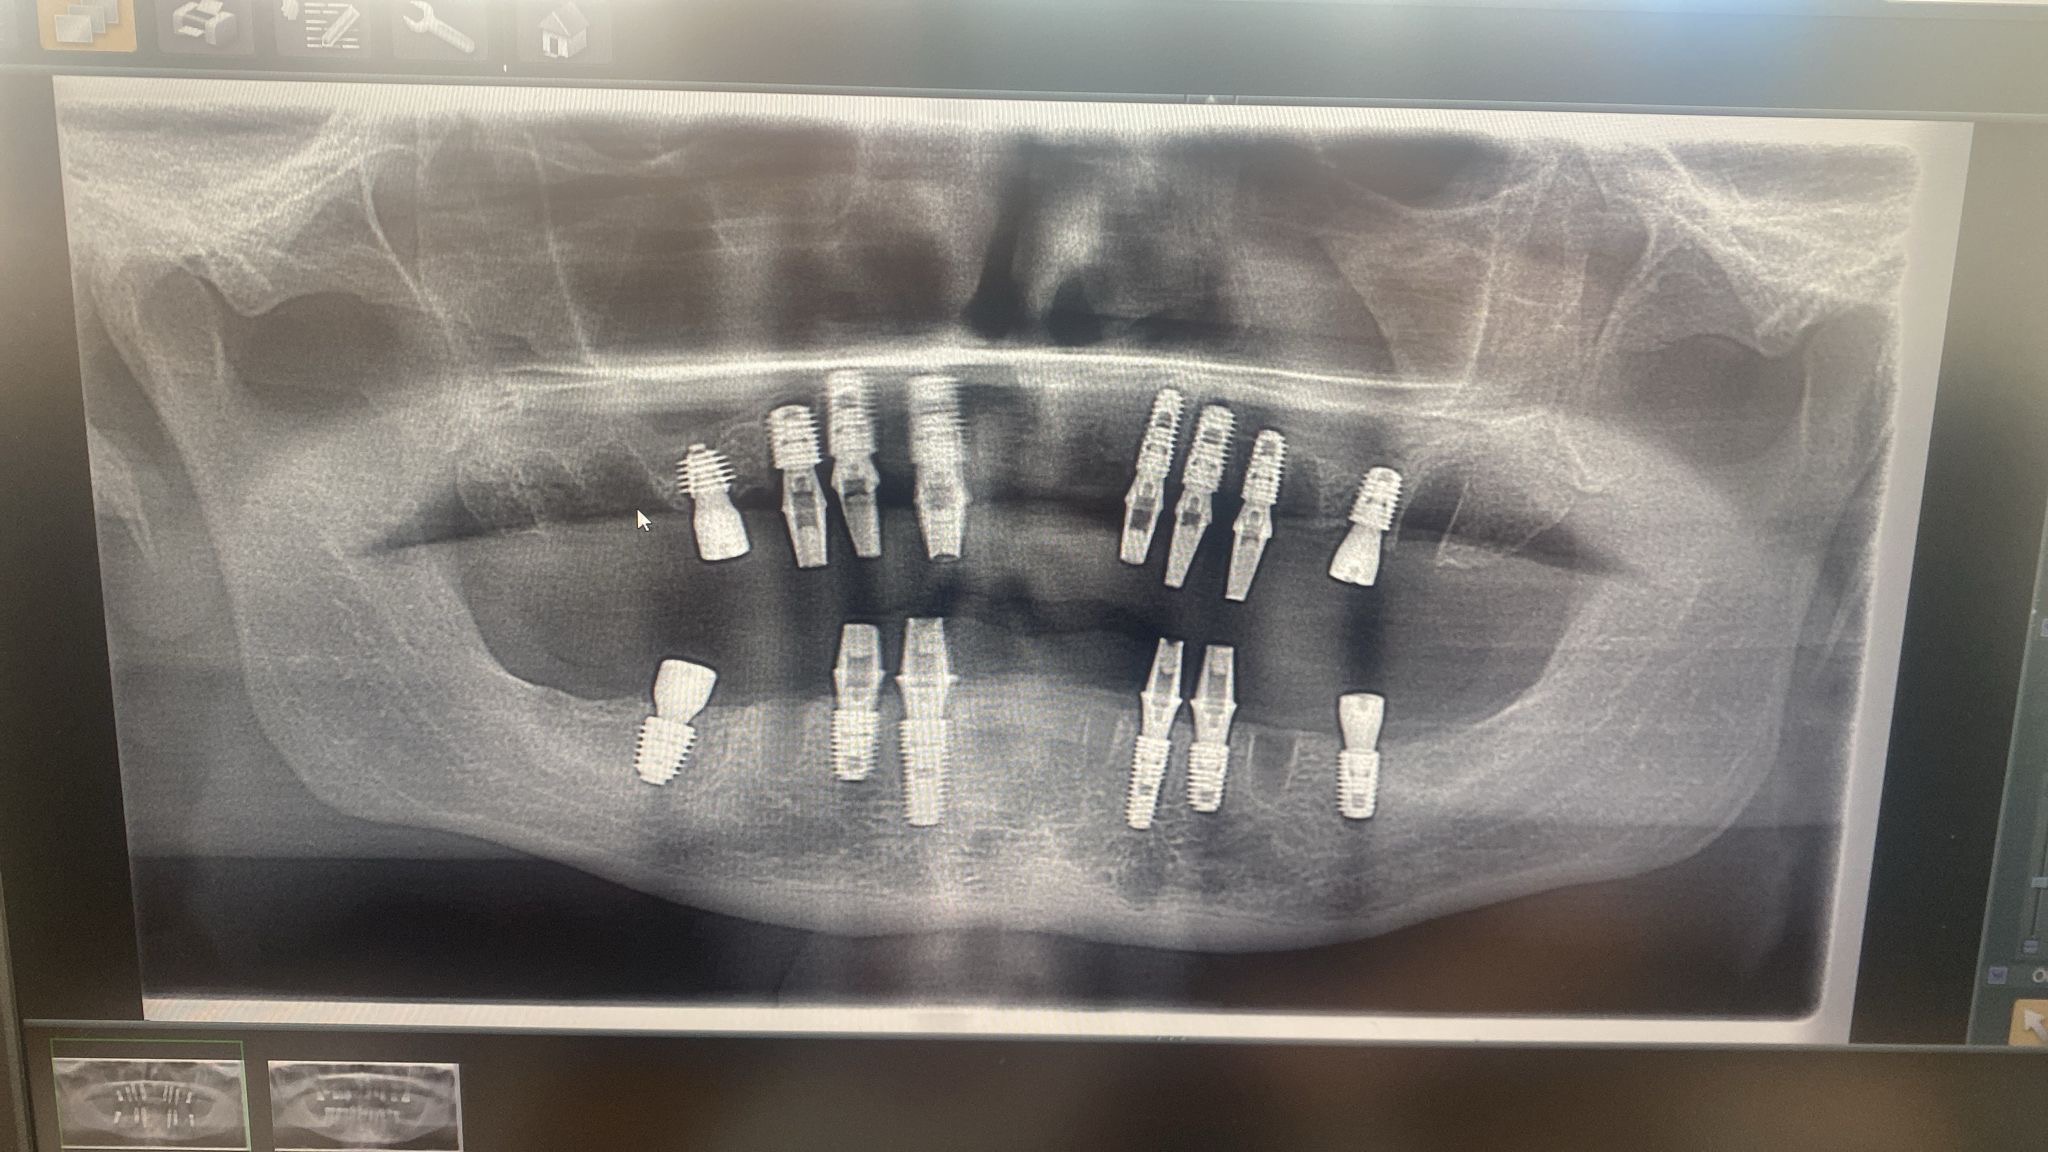

In January 2026, Jon travelled to the clinic for treatment. Unfortunately, the proper assessments he had been promised did not take place, and treatment went ahead anyway. All of his natural teeth were removed, and 14 implants were placed into his gums, with temporary teeth cemented on.

After a few weeks, his temporary teeth fell out, followed by severe pain. He had to return to the clinic, where he was told that two implants had failed and needed replacing. He was sedated again, at his own expense, for further treatment.

While he was under sedation, all of his implants were removed WITHOUT his knowledge or consent. Waking up to discover this was devastating.

Since having a 3D scan in the UK we have determined that the treatment abroad should never have gone ahead as Jon did not have sufficient bone to support the implants, this along with an infection they failed to treat. What bone he did have was damaged by implanting and removing implants. Sinus lift was also not carried out as told and very minimal if any signs of a bone graft were found on 3D scan. Jon had no ridge so dentures are not suitable for him and they just fall out, despite trying all adhesives recommended.